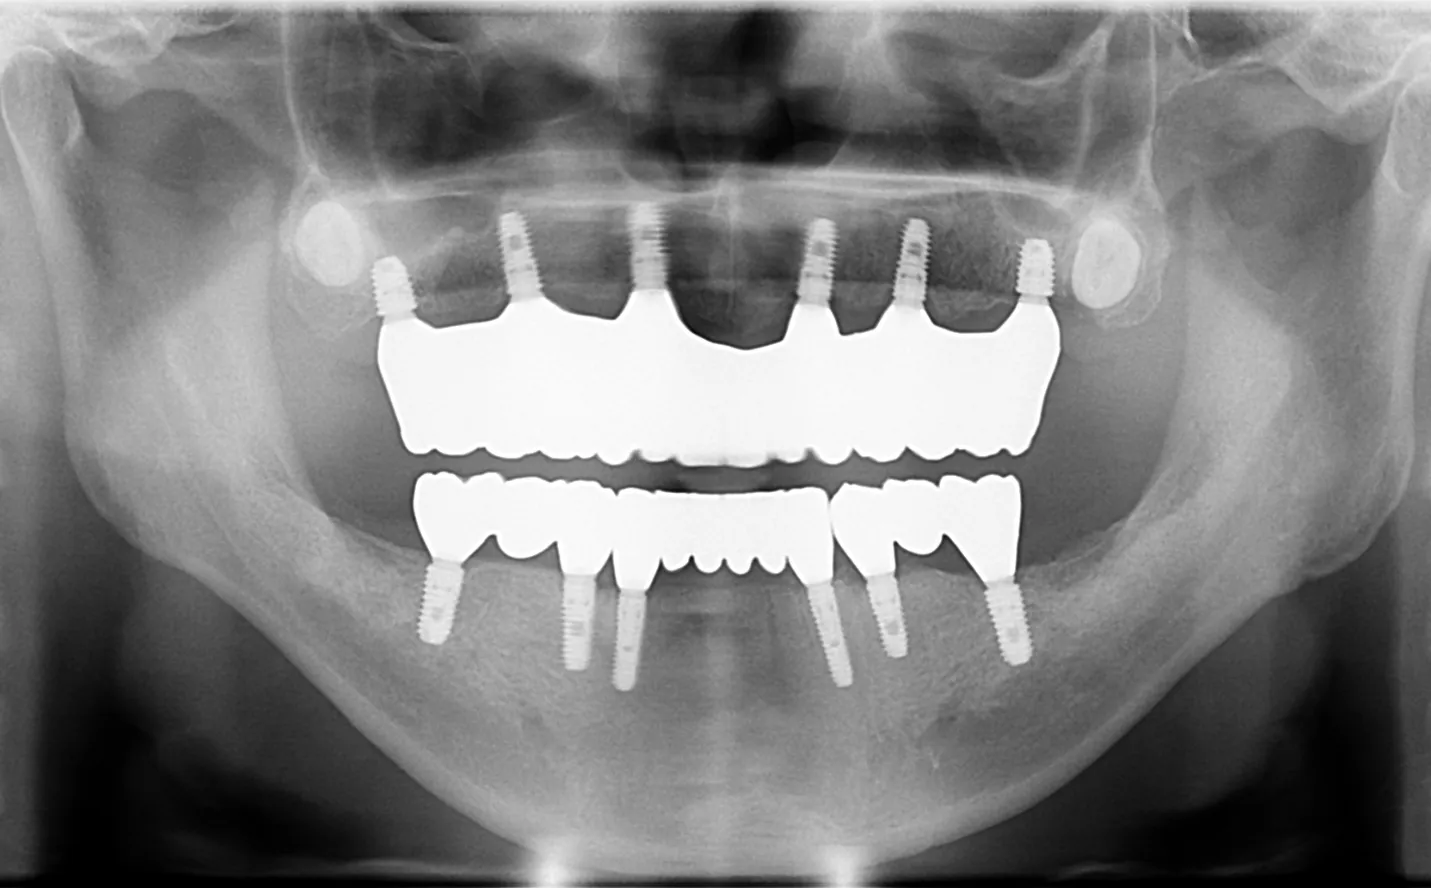

【症例1】

主訴

噛めない。不自由なく食事をしたい。

年齢・性別

50代男性

治療内容

上下顎フルインプラント

期間

1年2ヶ月

費用

7,279,000円